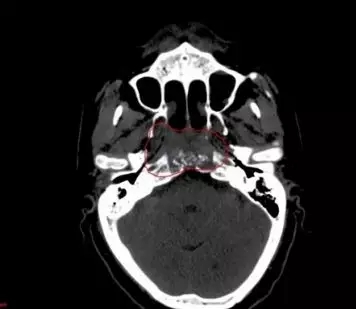

治疗前CT图像